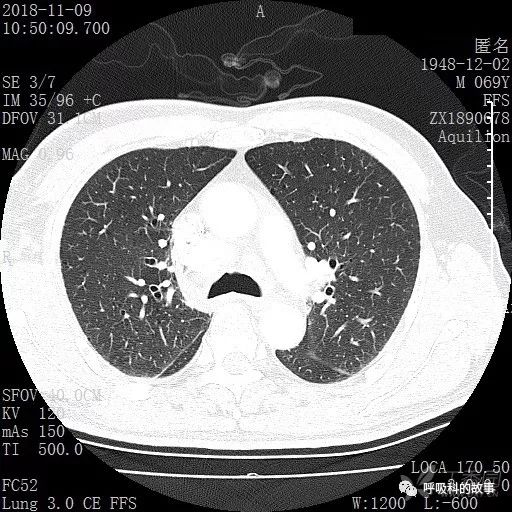

胸部增强CT示右肺门占位伴远端阻塞性肺炎,纵膈、右肺门、右侧颈根部、右侧腋下及肝门部肿大淋巴结。两侧胸腔少量积液。

肺窗CT